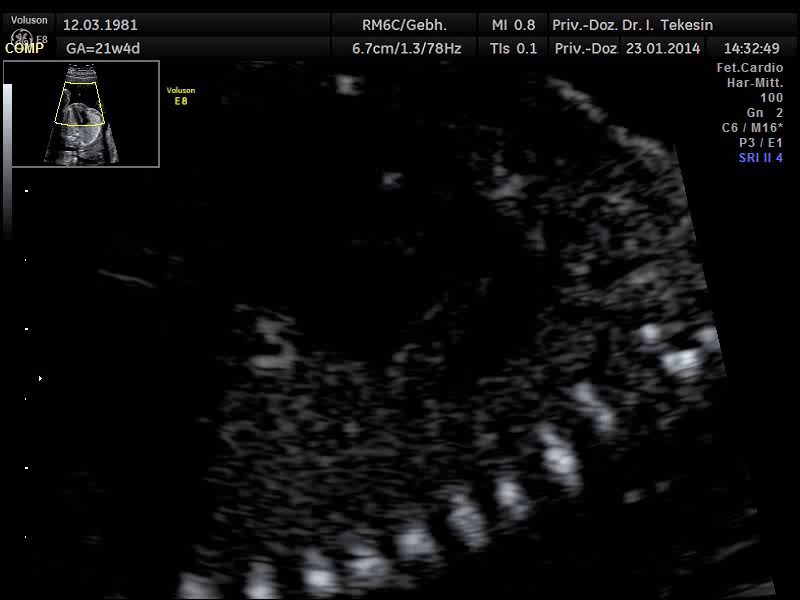

Fetale Echokardiographie

Ein weiterer Bestandteil der weiterführenden Ultraschall-Diagnostik ist die Beurteilung des kindlichen Herzens und der großen Blutgefäße, die fetale Echokardiographie. Dabei untersuchen wir die Lage, Größe und Symmetrie des Herzens, Anatomie der Herzstrukturen, Funktion der Herzklappen, Herzfrequenz und die Lage der großen Gefäße. Mit Hilfe der farbkodierten Doppler-Sonographie des Herzens werden weitere Details untersucht: die Funktion der Herzkammern, Herzscheidewände, Blutflüsse im Herzen und Blutflüsse in den großen Gefäßen.

Das Ziel dieser Ultraschalluntersuchung des fetalen Herzens ist der weitest mögliche Ausschluss von angeborenen Herzfehlern. Die Voraussetzung hierfür sind eine spezielle Ausbildung und Erfahrung des Arztes in Verbindung mit der hohen Qualität des Ultraschallgerätes.

Die endgültige Beurteilung des Herzens, seiner Funktion und der Blutflüsse, erfolgt jedoch erst zwischen 19. und 21. SSW und sollte in der Regel mit der 22./23. SSW abgeschlossen sein. Zu einem späteren Zeitpunkt in der Schwangerschaft ist die Diagnostik häufig durch die ungünstige Lage des Kindes sowie durch die schlechte Schalldurchlässigkeit der Rippen beeinträchtigt.

Normaler Vierkammer-­‐Blick

Normaler Vierkammer-Blick